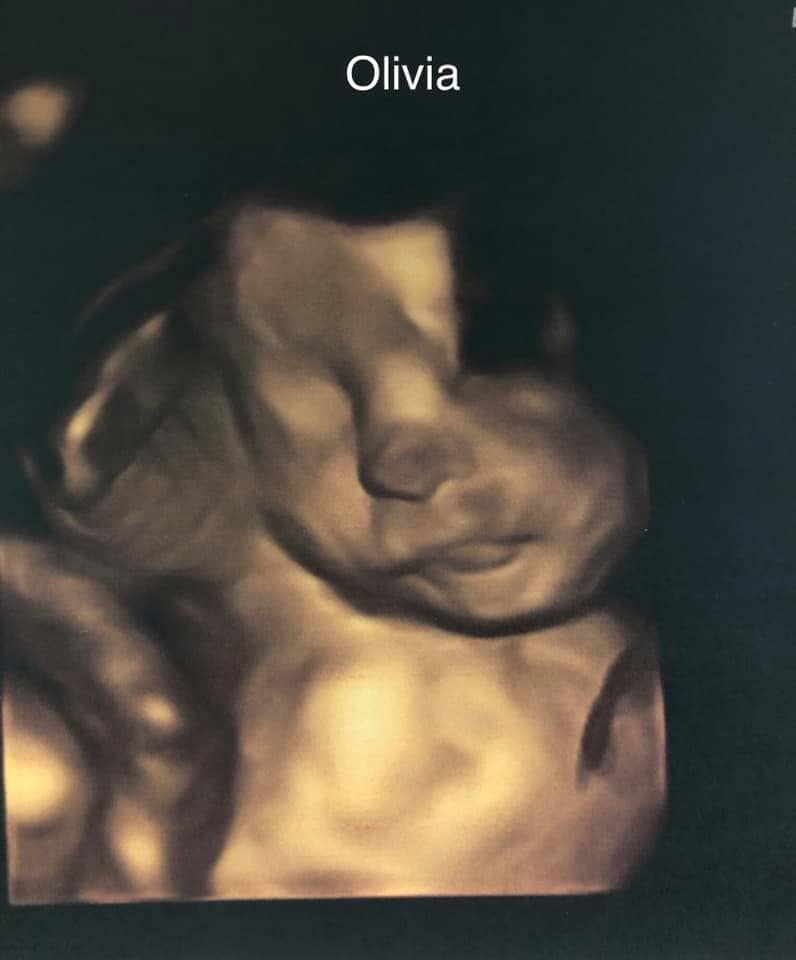

Ultrasound photos at 29 weeks pregnant with twins